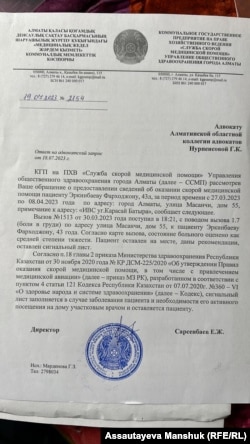

Адвокат Нұрпейісов Фарходжон Еркінбаев қамауға түскен күннен бастап азаптауға тап болғанын, оған сол күні полиция департаментіне медициналық жедел жәрдем шақыртылғаны дәлел болатынын айтады.

– Еркінбаев 30 наурызда күндіз ұсталған, ал сол күні кешкі алты жарым шамасында уақытша ұстау изоляторына жедел жәрдем шақыртылған. Жедел жәрдем қағазында "Масаншы көшесіндегі №55 мекенжайдағы Фарходжан Еркінбаевқа шақыртылғаны", кеудесі ауырып тұрғанын айтқан пациенттің жағдайы "орташа ауыр" деп бағаланғаны жазылған. Оны денесінің бүйрек тұсынан, ішінен және басқа жұмсақ жерлерінен ұрған. Соққы ізін жасыру үшін 15 күнге дейін ешкіммен кездестірмеген. Оны азаптағанын өздері жоққа шығарады. Бірақ ұрып-соқпаса, изоляторға сап-сау кірген адамға арада бес-алты сағат өткенде неге жедел жәрдем шақыртады? – дейді адвокат.